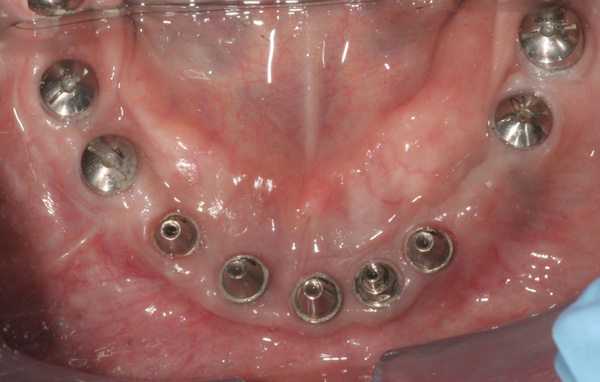

Background: In this case, the patient had a failing mandibular and maxillary dentition due to caries secondary to radiation-induced xerostomia. The patient had had a radical neck dissection to remove a squamous cell carcinoma of the throat 9 years prior to his prosthodontic consultation with the authors. The patient reported a history of radiation therapy following surgery, but did not have a shielding stent. A staged approach was used so as to avoid removable prosthetics on his severely dry soft tissues. He chose to treat his mandibular issues first. Figure 9 shows healing abutments next to the temporarily retained natural teeth, and Figure 10 shows the first-stage custom abutments inserted with relatively good gingival contour and no recession. Recession was clearly seen around all first-stage abutments following adjacent extractions and second-stage implant placement (Figure 11).

Figure 9 Healing abutments.

Figure 9

Figure 10  First-stage custom abutments.

Figure 10

Figure 11 Recession evident around first-stage abutments following adjacent extractions and second-stage implant placement.

Figure 11